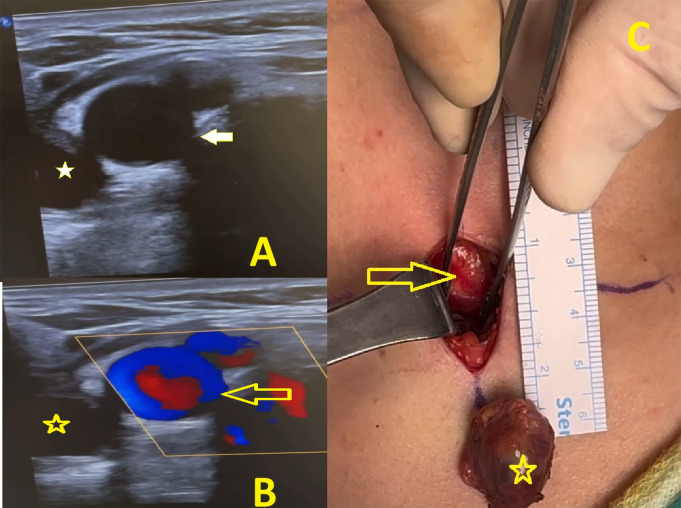

Purpose: One of the endocrine conditions that endocrinologists see the most frequently is primary hyperparathyroidism, which is brought on by a parathyroid adenoma. Minimally invasive parathyroidectomy (MIP) has become the first line of treatment for primary hyperparathyroidism due to solitary parathyroid adenoma. Surgeon-performed ultrasonography (SUS), which has been found to be extremely accurate in localizing aberrant glands, has been employed preoperatively to augment the sensitivity of high-resolution ultrasonography (hUS).

Methods: Two groups were randomly created from cases that underwent parathyroid surgery. In the first group, surgery was performed on 31 patients, taking into account the ultrasound results reported by radiology and the Technetium-99 m sestamibi scintigraphy results interpreted by the nuclear medicine clinic. In addition to the ultrasound results reported by radiology and the scintigraphy results interpreted by the nuclear medicine clinic, surgery was performed on 18 patients in the second group, that the surgeon applied ultrasound to them before the operation and separately evaluating the location of the parathyroid adenoma. Surgery time, hospital stay, pre and postoperative calcium and parathormon values were compared between the two groups.